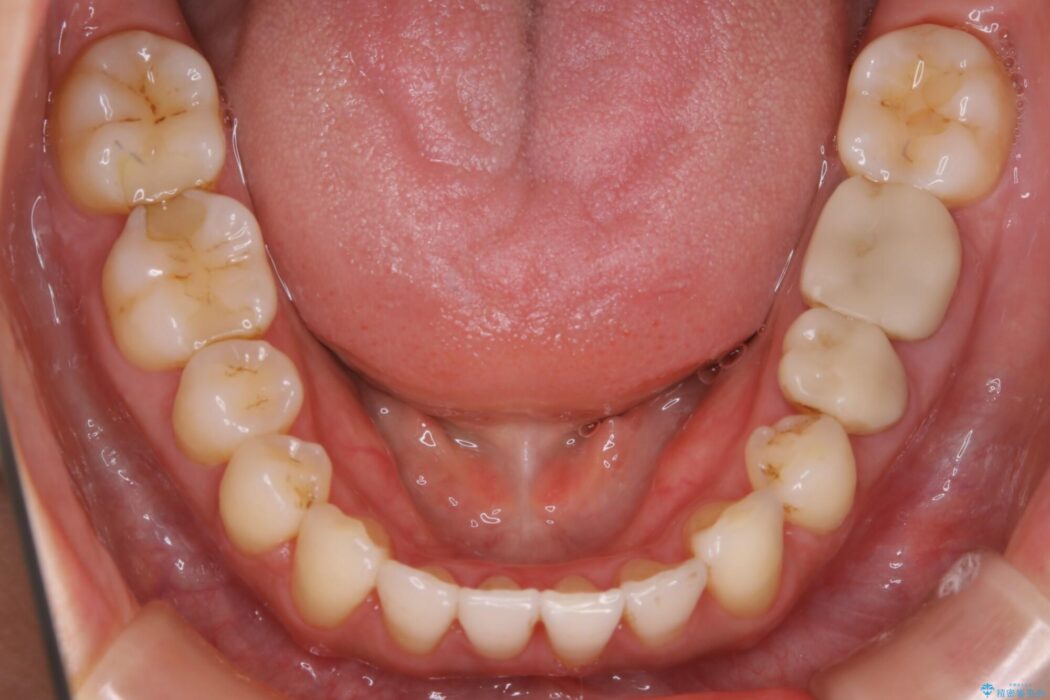

治療後について

笑った時の歯の見え方が改善され患者様にご満足いただけました。